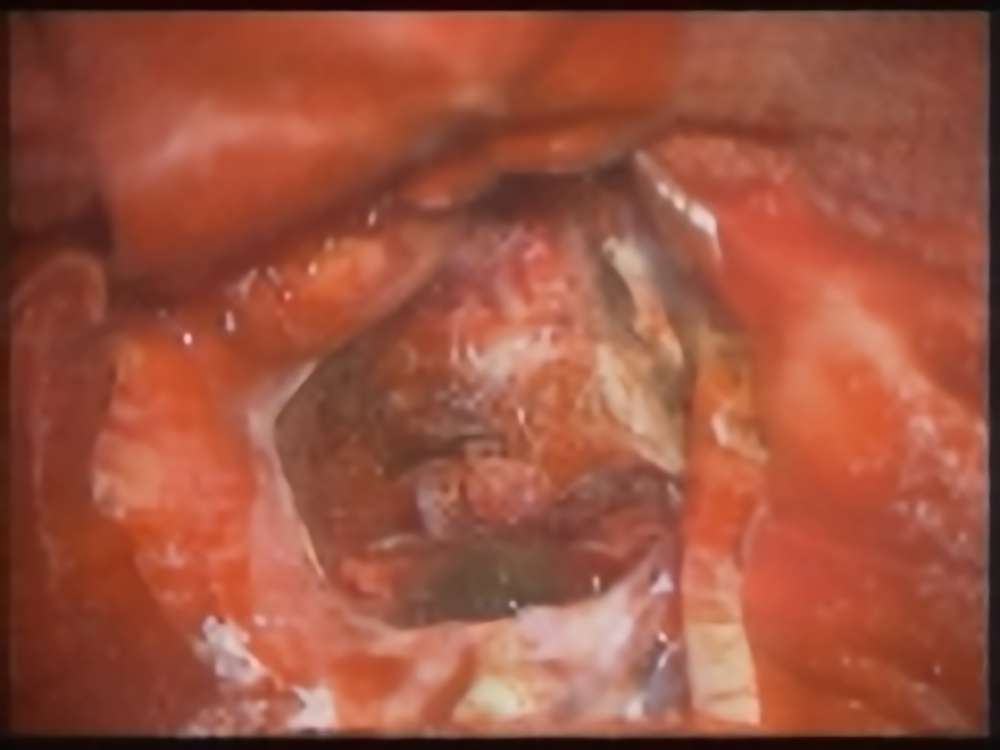

症例 '16年8月

No.

年_番号

手術年月

患者年齢

’16_126

'16年8月

60代

病名

術式

備考

髄膜腫

(傍矢状洞)

断層撮影

手術前

1

手術前2

手術後

術中写真

摘出 前

摘出 中

摘出 後